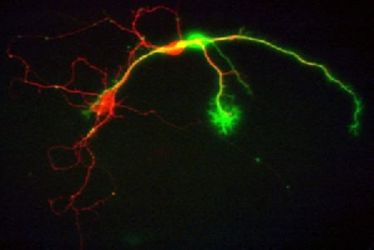

Neurologisches Seminar: Diabetes und Gehirn

Neurologisches Seminar: Diabetes und Gehirn